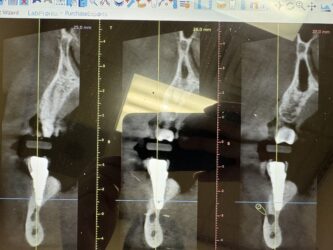

Dr. started the discussion #19 in the forum Implant Tx Planning 2 years ago

These are images of a recent scan.

This is 5 months after #19 implant was explanted (failed 2 weeks after placement) and simultaneous grafting was done.

I have currently planned for a Hiossen 4.5x7mm with buccal veneer grafting. This will be placed relatively deep due to ridge atrophy. What are your thoughts on this deep placement…